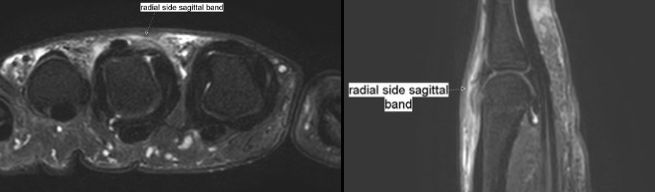

시상대는 중수지절(MCP) 관절을 둘러싸는 띠 모양의 구조물로, 신전건이 손가락 중앙에서 벗어나지 않게 고정합니다.

주로 중지(3번째 손가락)에서 가장 흔하게 발생하며, 요측(radial,엄지방향쪽) 시상대가 척측(ulnar,새끼손가락쪽)보다 9:1 비율로 더 자주 파열됩니다.

초음파: 시상대 파열의 위치와 범위, 신전건의 아탈구/탈구 여부를 동적 검사로 확인.

MRI: 복합 손상 또는 만성 손상에서 추가 평가에 사용.